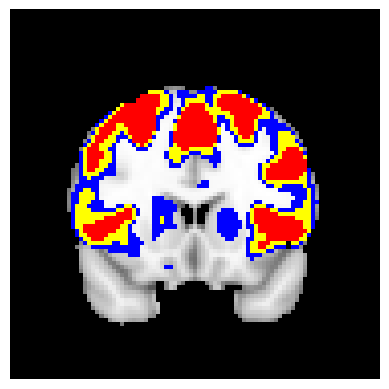

In this paper, we introduce testing-based confidence regions and which control the FDR over space in the upper and lower directions, respectively, with respect to the true excursion set . Our proposed approach uses one-sided testing at the level , instead of the usual two-sided testing, which allows us to control directional errors. We investigate two modes of multiple testing for confidence region construction: one using the Benjamini-Hochberg procedure, and the other using a two-stage adaptive procedure proposed in [blanchard2009adaptive]. This two-stage procedure is useful in increasing statistical power when the targeted excursion set is small, which occurs frequently for higher levels . Testing in the positive and negative directions separately we obtain confidence sets for each direction. We continue by constructing confidence sets with joint error control over the two directions, in which the tests for the positive and negative directions are considered together in a single multiple testing procedure. An illustration of the separate and joint confidence regions in practice is presented in Figure 1. We evaluate the performance of the proposed methods in terms of FDR, for type-I error, and false non-discovery rate (FNDR), for type-II error, defined with respect to the excursion set.

The confidence regions are constructed on fMRI scans from 77 subjects as a real data application of the proposed methods after applying additional smoothing with Gaussian kernel with FWHM to match the results shown in Bowring (2019) [BOWRING2019116187]. Confidence regions using 1) the joint method with , 2) the separate method with BH adjustment for upper and lower side each with , 3) the separate method with BH adjustment for upper side and two-stage adaptive procedure for lower with , and 4) SSS () were compared with threshold level 1.0%, 1.5%, and 2.0% Blood Oxygenation Level Dependent (BOLD) change. Joint control confidence regions are produced with instead of 0.05 for the reasons mentioned in chapter 3.

For all slices, FDR controlling methods show tighter inference of both upper and lower CR compared to the SSS method. SSS shows smaller upper CR and larger lower CR which suggests more conservative inference compared to FDR controlling testing based methodologies. This is due to the fact that by controlling for FDR, the method allows for more false discoveries in exchange for more discoveries in general. Despite having higher level at , joint control confidence regions still show comparable results to other methods even with higher significance level. Naturally, as the threshold goes up, the area enclosed between the upper and lower confidence regions decreases.